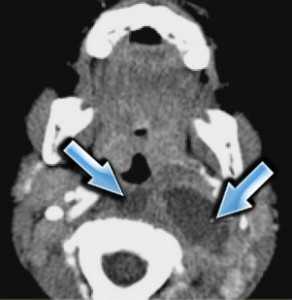

(Слева) УЗИ, поперечная проекция: визуализируется веретенообразная гипоэхогенная опухоль В и нижней трети шеи слева (известная локализация ПС). Обратите внимание на связь с корешками/ветвями ПС. На УЗИ в продольной плоскости (не показана) также определяется связь опухоли с плечевым сплетением - это подозрительный признак шванномы ПС.

(Справа) MPT (Т2 ВИ FS), аксиальная проекция: визуализируется шваннома ПС, связанная с корешком. УЗИ позволяет идентифицировать опухоль и отличить ее от лимфоузлов, чаще встречающихся в этой области. (Слева) УЗИ, поперечная проекция: визуализируется солидная гипоэхогенная опухоль с задним усилением, лежащая между передней и средней лестничными мышцами. Расположение в перивертебральном пространстве и УЗ-картина являются диагностическими признаками шванномы ПС.